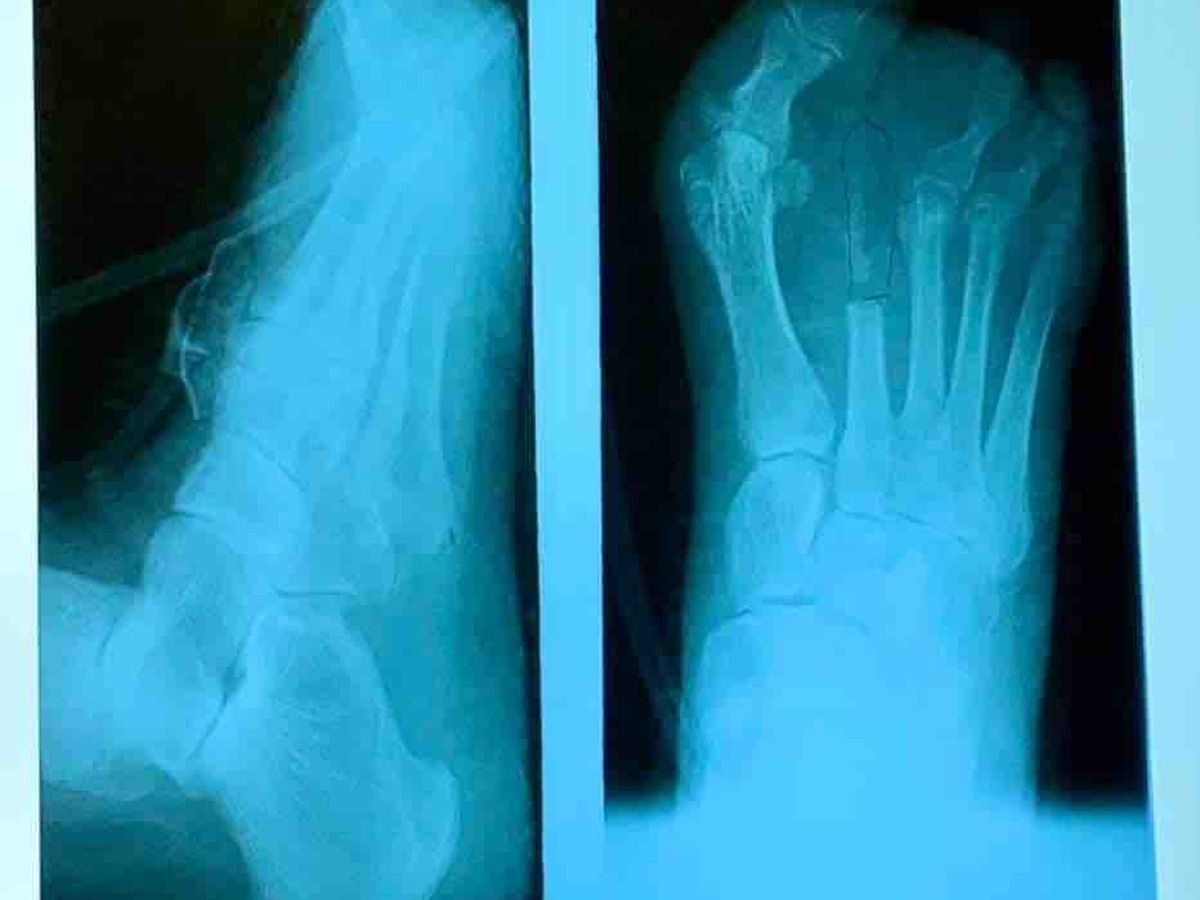

days with a very serious infection. She was diagnosed with osteomyelitis in her left

foot and had to have her 2nd toe amputated. She then had to have a 2nd surgery to

remove part of a bone to make sure margins were clear of the infection. She’s been at home on her own for just about 3 weeks .